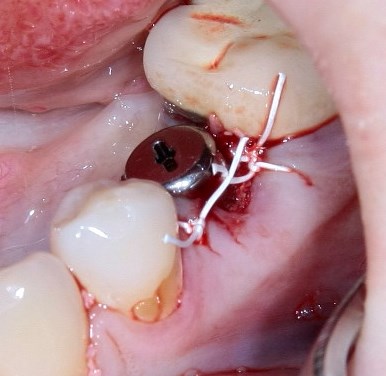

Немедленная имплантация — оптимальное решение в любой клинической ситуации